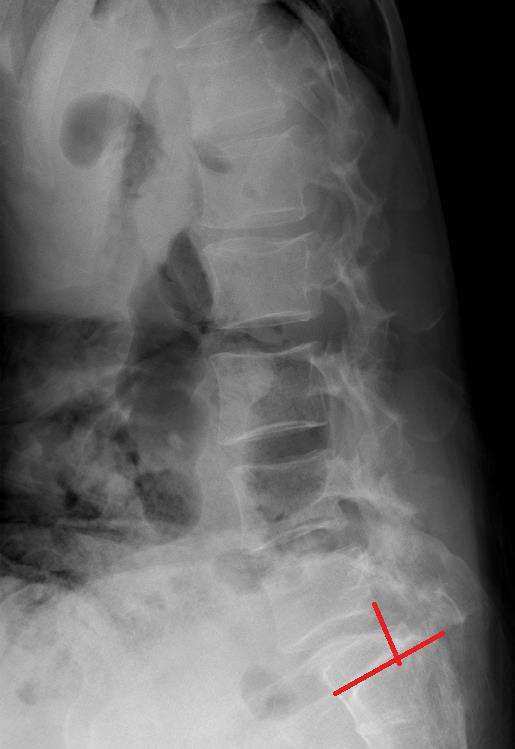

65세의 척추 전방 전위증 환자의 사진입니다.

측면상에서 보면 1단계 정도로 척추가 앞으로 밀려 나간 모습이 보입니다. 상부요추의 후만이 일어나고 요추 5번과 천골과의 접합부분은 퇴행화 현상도 관찰됩니다.